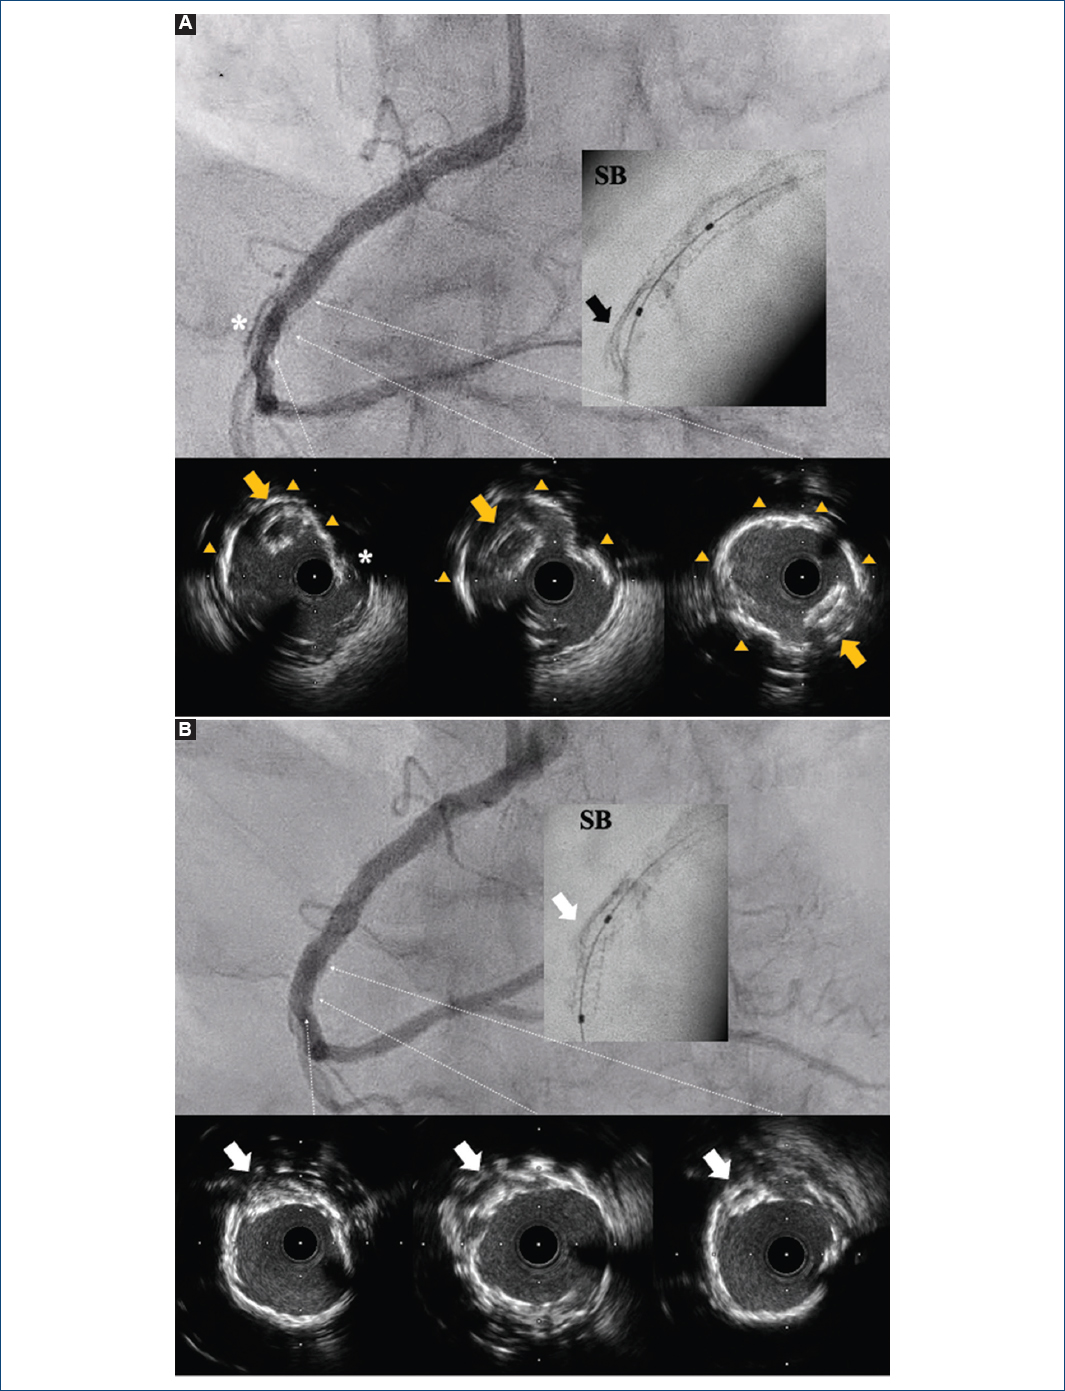

El ultrasonido intravascular localizó el stent desprendido, parcialmente aplastado y no expandido, distal al stent implantado previamente, con pérdida de su posición con la guía de angioplastia, destacando además calcificación y disección distal de la arteria coronaria derecha (Fig. 2A). Las imágenes de Stent Boost (Philips Medical Systems, Eindhoven, Países Bajos) en una proyección alternativa confirmaron la ubicación del stent desprendido, inicialmente difícil de visualizar por la superposición con la calcificación y la disección coronaria (Fig. 2A). Los intentos de extracción fracasaron, por lo que se optó por aplastarlo contra la pared vascular con balones no distensibles, seguido del implante de un stent liberador de everolimus (Fig. 2B). La evolución de la paciente fue normal.

Figura 2 A: imágenes de angiografía coronaria y ultrasonido intravascular que muestran la disección coronaria distal (asteriscos), la presencia de calcificación circunferencial de la arteria coronaria derecha (triángulos) y una imagen ecogénica elíptica dentro de la luz coronaria correspondiente al stent desprendido y no expandido (flechas amarillas), confirmada por la imagen de Stent Boost (SB) (flecha blanca). B: imágenes de angiografía coronaria y ultrasonido intravascular tras aplastar el stent desprendido (flechas blancas), y resultado del tratamiento exitoso de la disección coronaria con un stent liberador de everolimus de 3.0 × 18 mm.